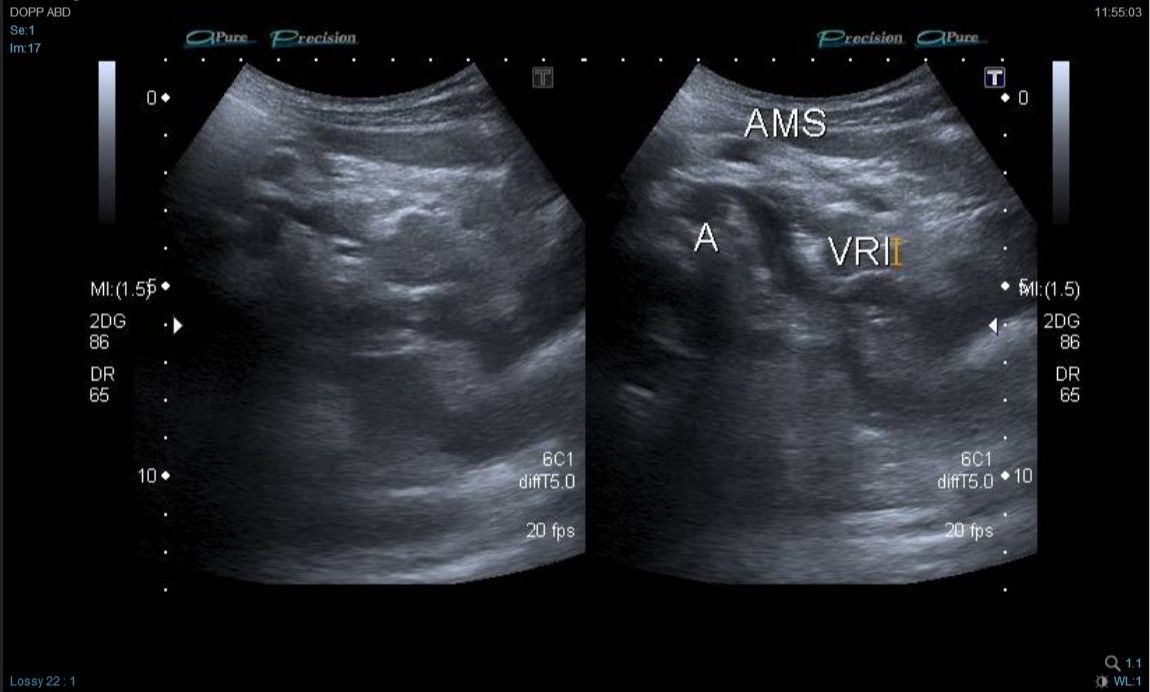

Por la edad del paciente (por evitar la irradiación) y la sospecha clínica, se decidió realizar primero nueva ecografía Doppler (Fig. 1) por personal experto y dirigida con la sospecha de síndrome del cascanueces, observándose una mínima dilatación de la vena renal izquierda en su salida y provocada posiblemente por la salida de la arteria mesentérica superior (pinza aortomesentérica). Se identificó también una disminución de la velocidad con respecto a la vena renal derecha. Estos hallazgos confirmaron la sospecha clínica de síndrome del cascanueces por compresión de vena renal izquierda por pinza aortomesentérica.

| Figura 1. Imagen ecografía Doppler. Mínima dilatación de la vena renal izquierda en su salida, provocada posiblemente por la salida de la arteria mesentérica superior (pinza aortomesentérica) |